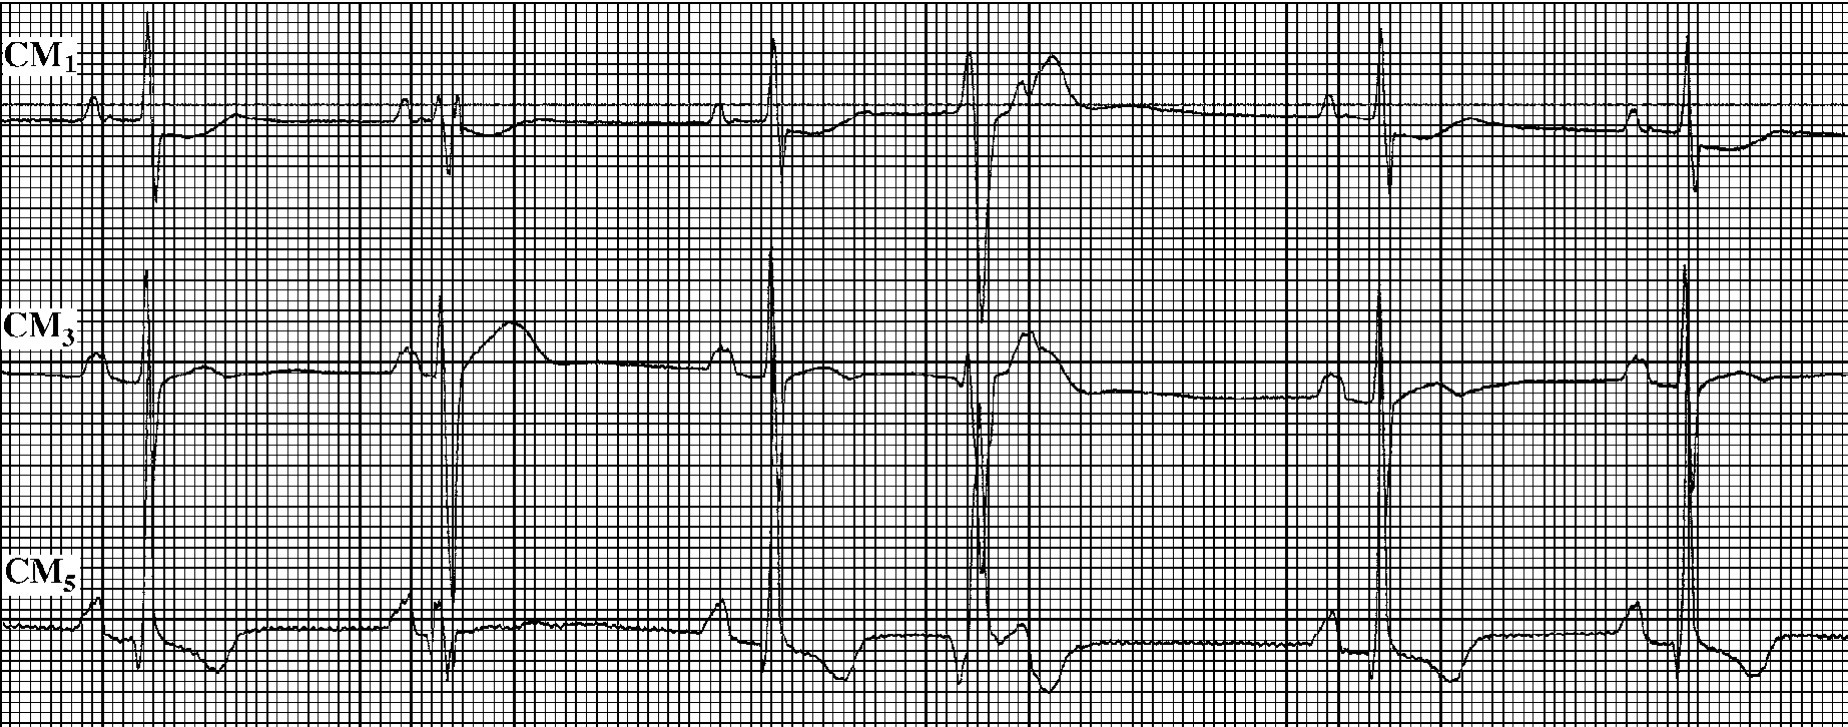

(4)出现特别长的R-R间期 房性激动如在房室交界区连续发生隐匿性传导,可形成特别长的R-R间期,甚至发生阿—斯综合征(图43-3)。

img749

图43-3 心房颤动出现意外延长的逸搏周期

两图连续描记,上图E为交界性逸搏,因2个长的R-R间期相等;下图的长R-R间期比逸搏周期还长,提示有隐匿性传导,使本应出现的交界性逸搏延迟出现